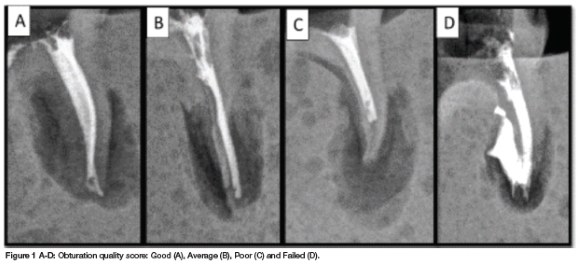

The presence of voids (Score 1-4) and the extent of fill (Grade A-D+) were combined to grade obturation quality (Table 1). Each tooth was graded as "good", "average", "poor" or "failed" (Figure 1).

The obturation outcomes observed across the three instrumentation groups differed significantly (p = 0.016). This was followed up by pair wise comparisons for each obturation outcome.

The proportion of "good" obturation outcomes observed with the ProTaper Gold SX group (65%) was significantly higher than observed in the K-file group (25%, p = 0.025) but was similar to the proportion of "good" outcomes observed in the WaveOne Gold Medium group (55%, p = 0.748). The proportion of "average" obturation outcomes was similar across the three groups (Table 2). The proportion of "poor" obturation outcomes was significantly higher in the K-file group (40%) than that observed in the ProTaper Gold SX group (5%; p = 0.020). No other significant differences were observed (Table 2).